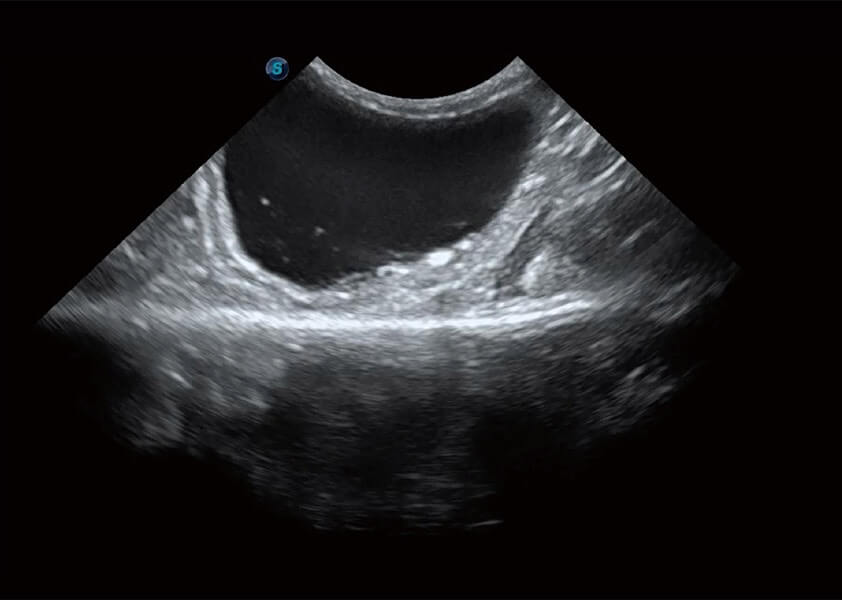

优异的基础图像

(犬)肾脏血流

(犬)胆囊泥沙